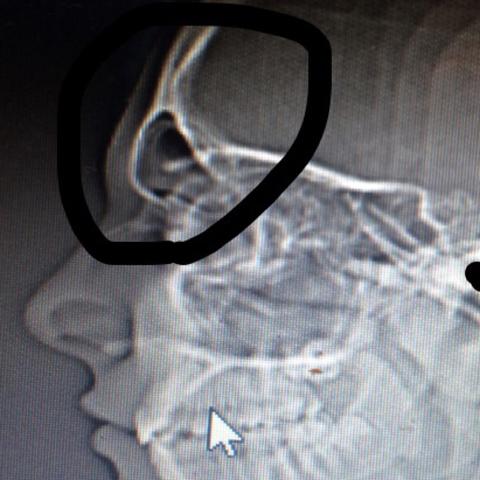

Computertomographie Bluterguss Medizin Radiologie Hamatom